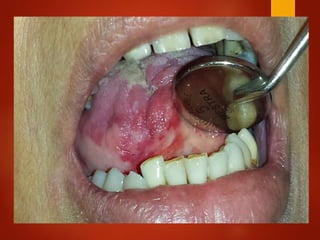

El documento es un registro médico odontológico que muestra las fechas de las visitas de un paciente al centro de salud El Raval, incluyendo exámenes y tratamientos realizados como la extracción de cálculos salivales en abril y mayo de 2012.